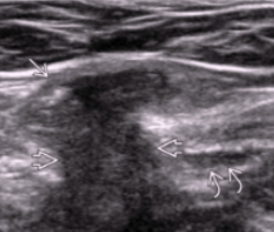

Strangulated hernia

Contents compressed → compromised blood supply → ischemia, necrosis, obstruction

Increased mortality & morbidity

US appearance

Thickened bowel wall, absent vascular flow, free fluid, no peristalsis